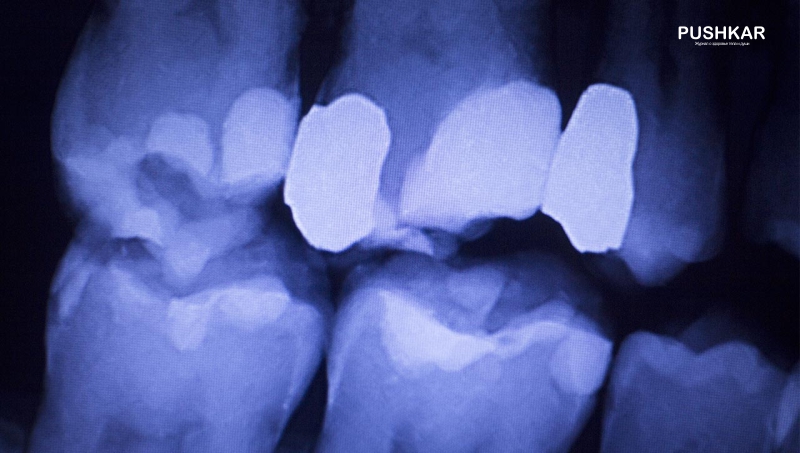

Кариес является основным фактором риска потери зубов у людей всех возрастов. Кариес, пародонтит и периодонтит являются инфекционными заболеваниями, вызванными бактериями.

Таким образом, кариес является инфекционным заболеванием. Бактерии, такие как Streptococcus Mutans, производят кислоты из сахаров, которые деминерализуют зубную эмаль и дентин (костное вещество зуба).

Первичным фактором риска для возникновения кариеса зубов являются сладости. Ультрафиолетовое излучение (УФИ) от солнечных лучей и прием добавок витамина D может снизить риск развития кариеса